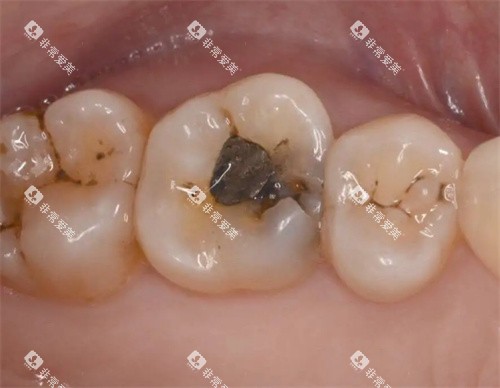

补牙是口腔科常见的治疗项目之一。

如果牙齿出现龋齿,就需要及时补牙。

娄底市中心医院口腔科根据补牙材料的不同,收费也有所差异。

普通树脂补牙材料价格相对较为亲民,每颗牙齿的收费在 200 - 300 元左右。

这种材料具有较好的耐磨性和美观度,能够满足大多数患者的需求。

如果选择进口的高端树脂补牙材料,其收费会相对较高,每颗牙齿大约在 400 - 600 元。

这类材料在颜色、硬度和粘结性等方面表现更为出色。